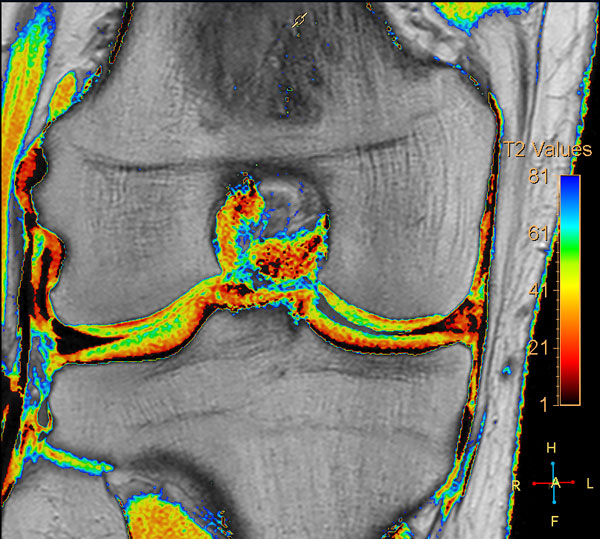

Comprehensive 3D knee imaging with MSK VIEW